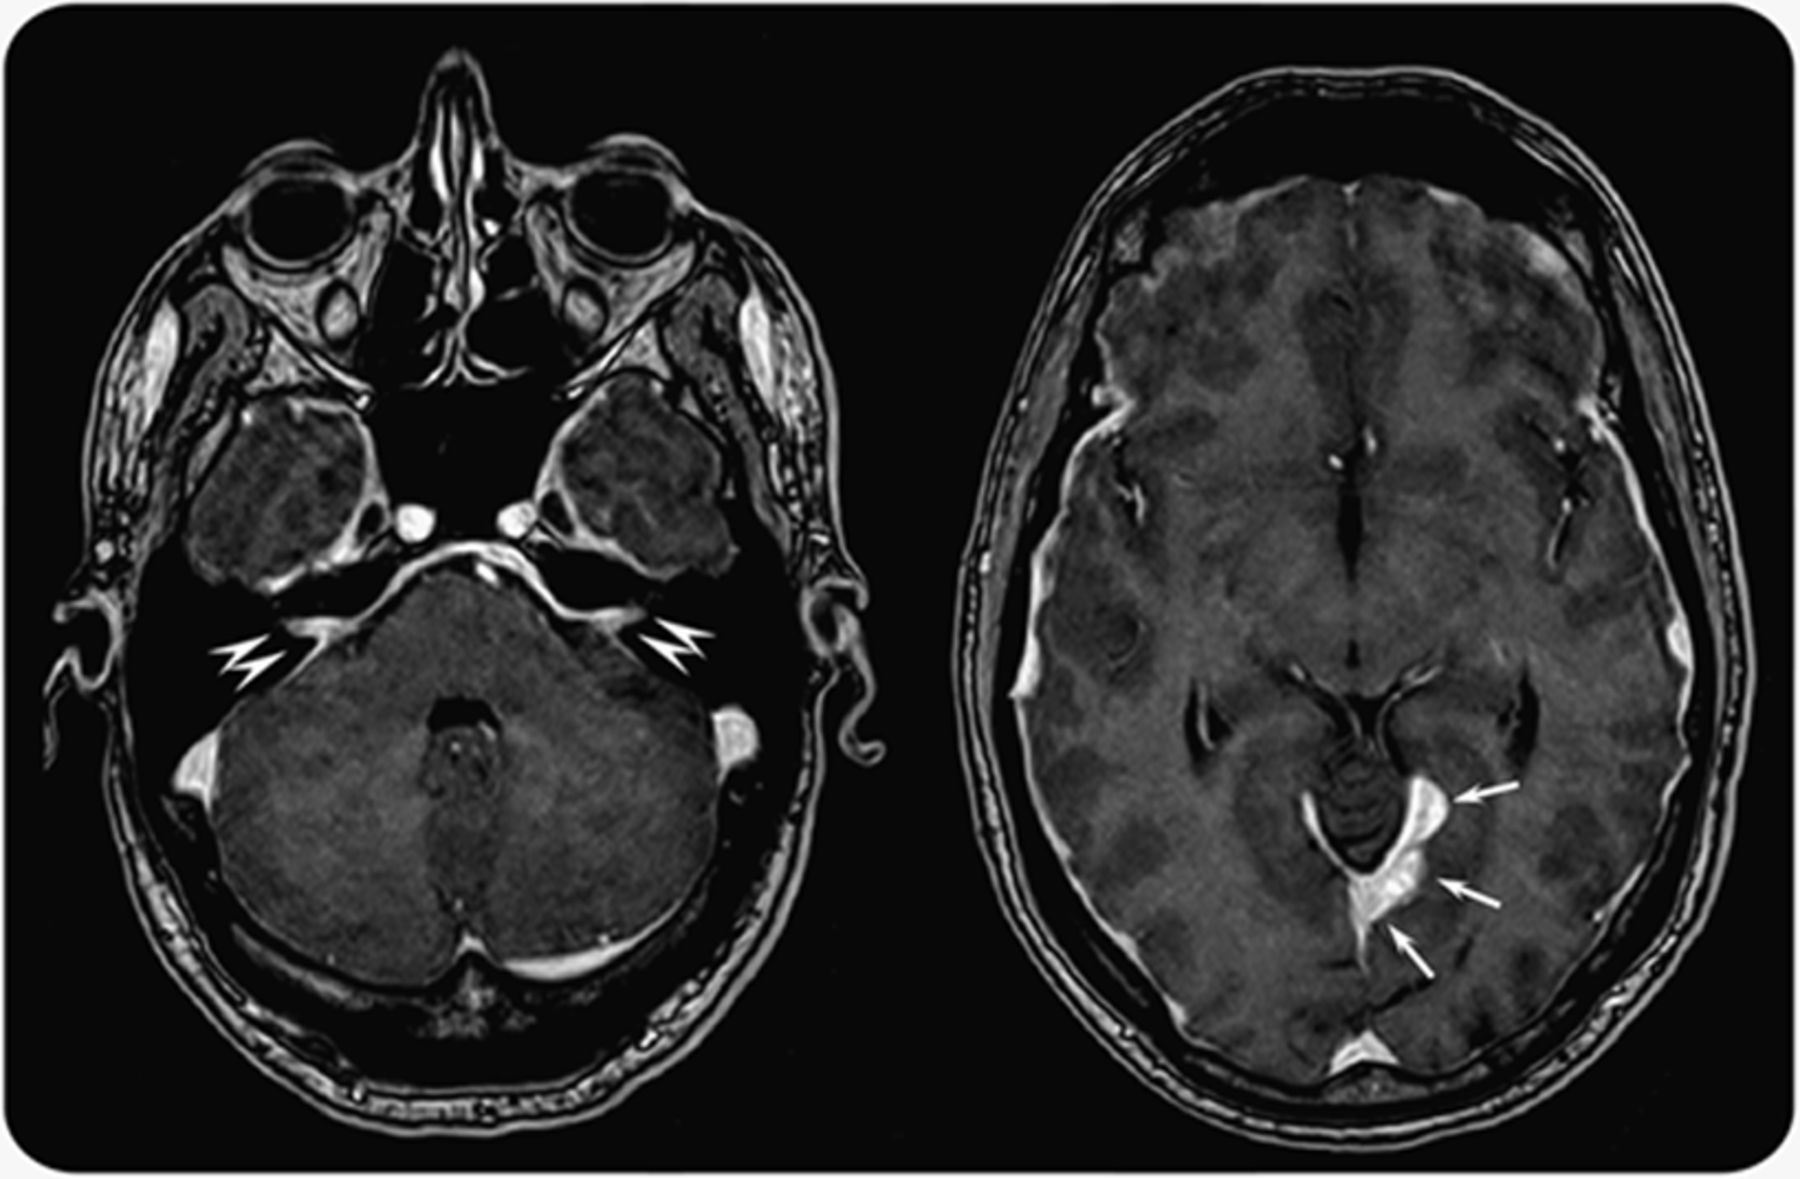

一名46岁男子与进步的视力丧失接受脑多病灶的MRI显示结节pachymeningeal涉及视神经脑膜增厚双边和内部声学道硬脑膜(图1)。扩散meningiomatosis被诊断和放射治疗有症状稳定。四年后,留给发生听力损失和对听觉减退,轻微的瞬态高剂量地塞米松后改善。血清免疫球蛋白(Ig) G4增加。CSF分析显示增加蛋白质、寡克隆免疫球蛋白、浆细胞和淋巴细胞。脑活检显示脑膜的浆细胞肉芽肿与IgG4-positive多克隆浆细胞和淋巴球浸润(图2)。IgG4-related疾病被诊断。1美罗华是不成功的。IgG4-related疾病是fibroinflammatory multiorgan块状病变和簇状条件特点是lymphoplasmacytic富含IgG4-positive浆细胞浸润可能影响每个器官;血清IgG4可能较高。尽管IgG4-related与独家多病灶的中枢神经系统疾病定位极其罕见,常误诊,2,- - - - - -,4它应该考虑类肿瘤的鉴别诊断颅内病变和hyperthrophic硬脑膜炎。